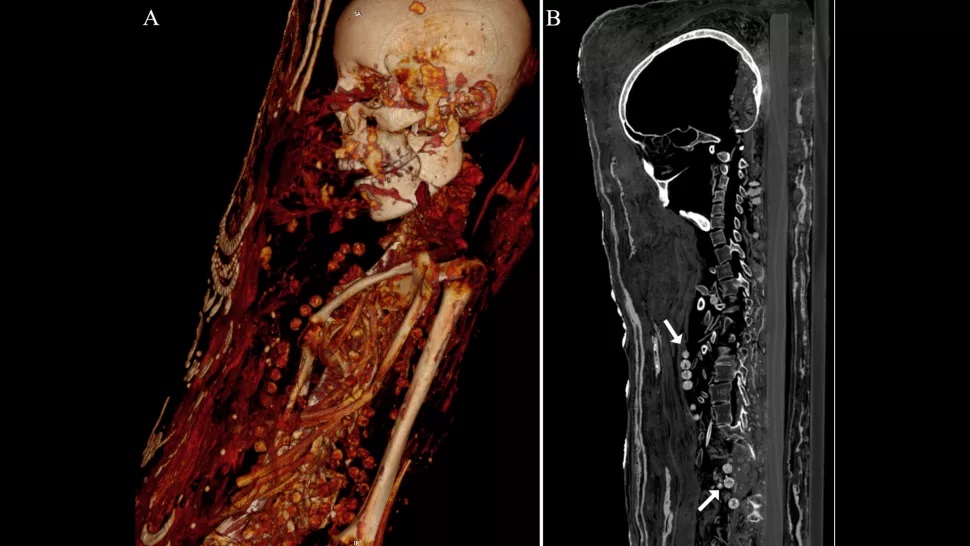

Обидві мумії, а також третя, виставлена в Єгипті, є єдиними відомими збереженими "портретними муміями з ліпними прикрасами" з Саккари, стародавнього єгипетського некрополя. На відміну від інших мумій, які були поховані в гробах, цих людей поміщали на дерев'яні дошки, обертали тканиною і "красивим саваном мумії" і прикрашали тривимірним гіпсом і зображенням всього тіла.

Комп'ютерна томографія показує, що принаймні одна з цих трьох портретних мумій була похована з органами (навіть з мозком), і що дві жінки були поховані з красивими намистами.

Після смерті цих людей - чоловіка, жінки і дівчинки-підлітка, час життя яких датується пізнім римським періодом (30 р до н.е. - 395 р н.е.) - їх мумії були поховані з артефактами, які, ймовірно, вважалися корисними в загробному житті, включаючи монети, які можливо, призначалися для оплати Харона, римського і грецького божества, яке, як вважалося, перевозило душі через річку Стікс.

КТ також виявила кілька проблем зі здоров'ям, у тому числі артрит у жінки.